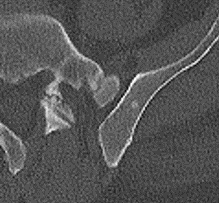

Figure 2: Qualitative results of bone lesion detection. Each column shows a cropped slice with the top row displaying ground-truth (green) and the bottom row showing nnUNet predictions (yellow). (a) shows a TP osteolytic lesion; (b) shows the prediction of a real osteoblastic lesion that was not prospectively marked as ground-truth (before review), and after GT review, it was correctly considered as ground-truth; (c) shows an osteolytic lesion not annotated in ground-truth before review and correctly marked afterwards. A FN adjacent to it is also shown. (d) shows a rare FP on the cortex of a rib.

Results. Qualitative and quantitative results of our model are presented in Fig. 2 and Table 1 respectively. Our model achieved a precision of 96.7% and a recall of 47.3% for detection of bone lesions (lytic, blastic, and mixed). We observed that the model was very confident in its predictions as demonstrated by the vast number of actual lesion predictions (TPs) compared against the FPs. Despite the high precision, the model was not very sensitive to the detection of bone lesions due to the large number of FNs.